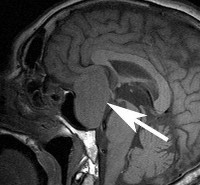

Нейровизуализацию опухоли гипофиза позволяет осуществить рентгенография черепа и зоны турецкого седла, МРТ и КТ головного мозга. Рентгенологически могут определяться увеличение размеров турецкого седла и эрозия его дна, а также увеличение нижней челюсти и пазух носа, утолщение костей черепа, и расширение межзубных промежутков. С помощью МРТ головного мозга возможно увидеть опухоли гипофиза диаметром менее 5 Компьютерная томография подтверждает наличие аденомы и ее точные размеры.